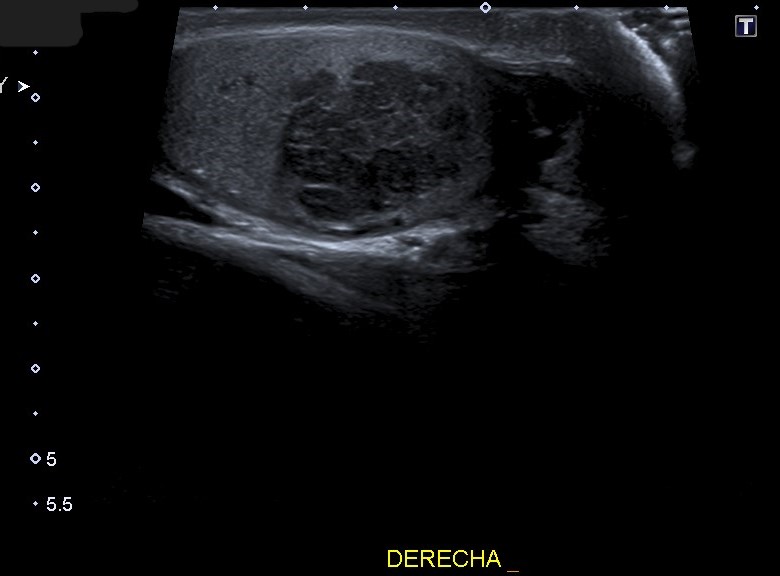

Hallazgos ecográficos

Ecografía escrotal: En testículo derecho se aprecia lesión heterogénea de predominio hipoecogénico con alguna calcificación grosera, polilobulada, de bordes mal definidos, con medidas aproximadas de 36 mm de diámetro máximo, con vascularización en su interior en el registro Doppler, sugestivo de proceso neoformativo testicular. No se objetiva engrosamiento epididimario ni de cubiertas escrotales.